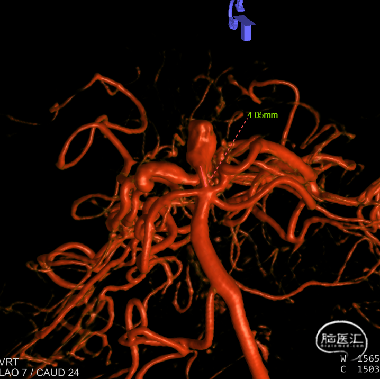

右侧颈内3D

动脉瘤参数:

动脉瘤大小为6.8*9.7mm,瘤颈宽4mm

载瘤动脉(颈内动脉)近端狭窄处为1.7mm,近端末狭窄处为1.4mm,远端为2.4mm。